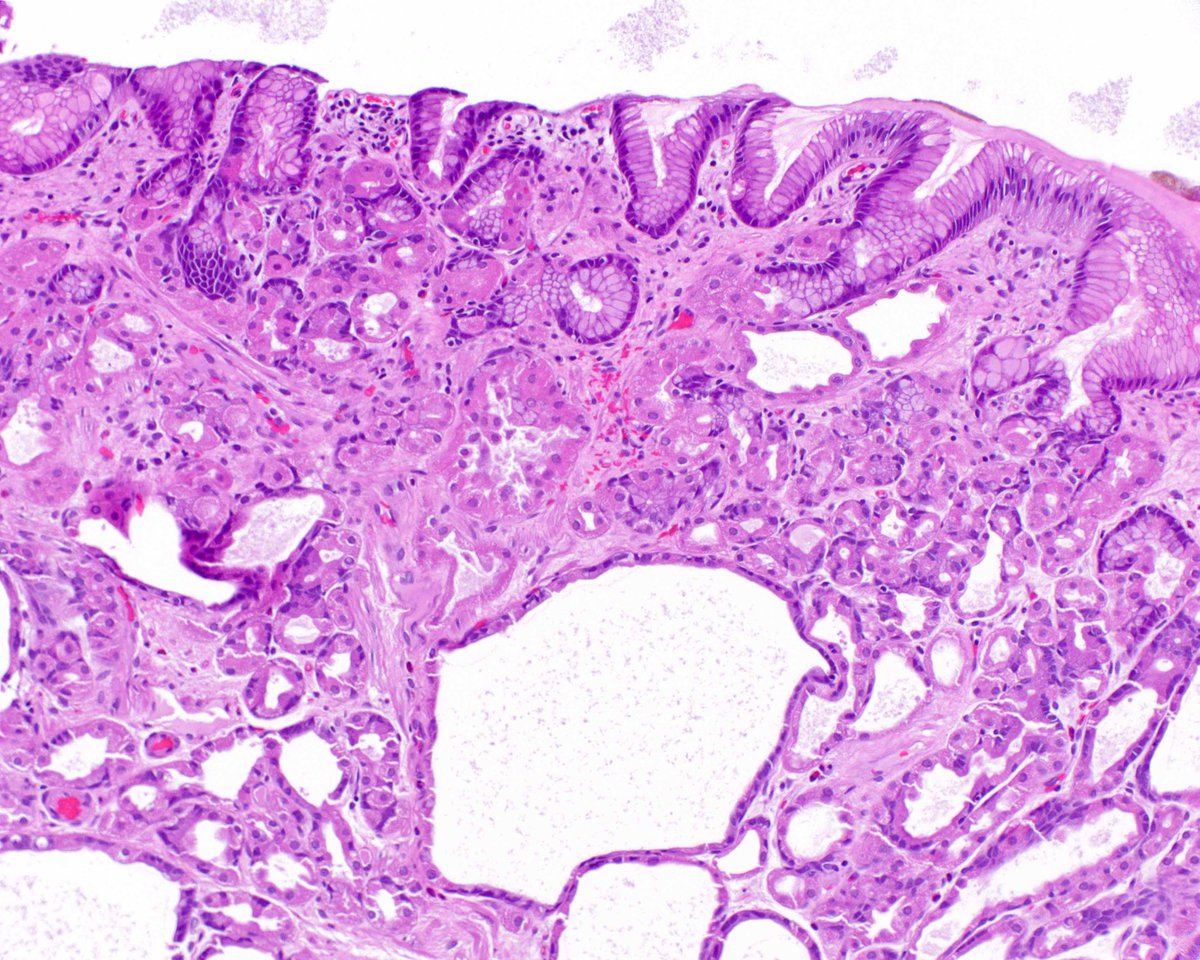

4.3 cm renal mass confined to kidney, tumor cells are predominantly with proliferative, tubular pattern 🎨 CK7 positive (strong, diffuse) 🎨 CD117 negative Thoughts? Sean R Williamson MD Kiril_T_Can Michelle_Hirsch (Donovan) Priya Rao, MD Ankur Sangoi

Kidney, young F adult #gupath Dr. Luca Olaleke Folaranmi Aurélien Morini, MD, MSc 🇫🇷🇪🇺💙💛 Celina Stayerman MD 🔻Nusrat Zahra🔻🇵🇸 @miss_me1986 Gonzalo De Toro Tristan Rutland MBBS FRCPA IFCAP Anandi Lobo, MD Sumanta Das Lorand Kis Erik Kouba bansar Carlos Miguel Ruiz Carlos Nieves Padma Priya J Susan Prendeville @AkgulMd Ankur Sangoi Barry McGinn